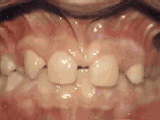

Spacing of teeth

Patient was bothered by the spaces between his teeth. Braces closed the spaces and gave him an ideal bite in twenty-four months. Special glued-in retainers help keep the spaces closed.